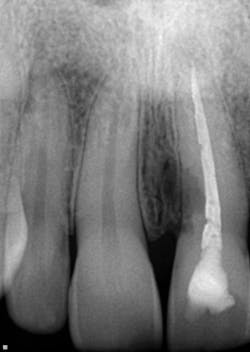

One-and-a-half years post-trauma (figure 8):

- The patient worked out of town for a period of time and then presented for his recare exam.

- The patient reported no concerns from his incident and was ready to move forward with tooth replacement.

- Radiographic examination of the maxillary anterior teeth revealed an uneven, corrugated-like radiolucency on the mesial aspect of No. 9 that extended just below the CEJ almost to the coronal half of the tooth.

- No. 9 was not tender to palpation, probing depths circa were 3 mm to 4 mm, and the bite test was normal.

Diagnosis: Trauma-induced external resorption

Figure 8